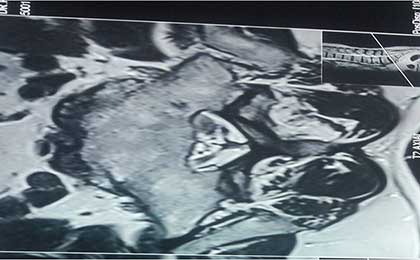

AXIAL WITH LEFT SEQ DISC 3